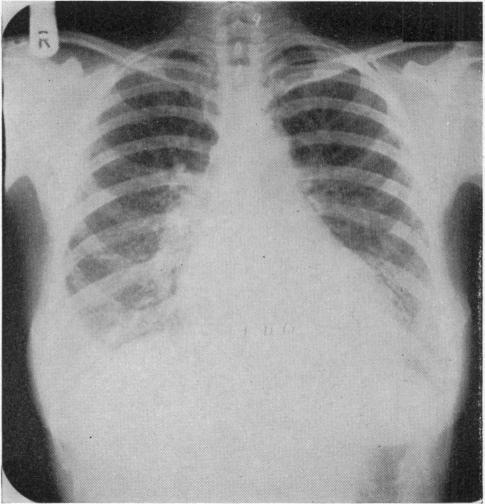

An Unusual Case of Renal Failure and Hypertension.

Br Med J. 1963 Jul 20;2(5350):167-70.